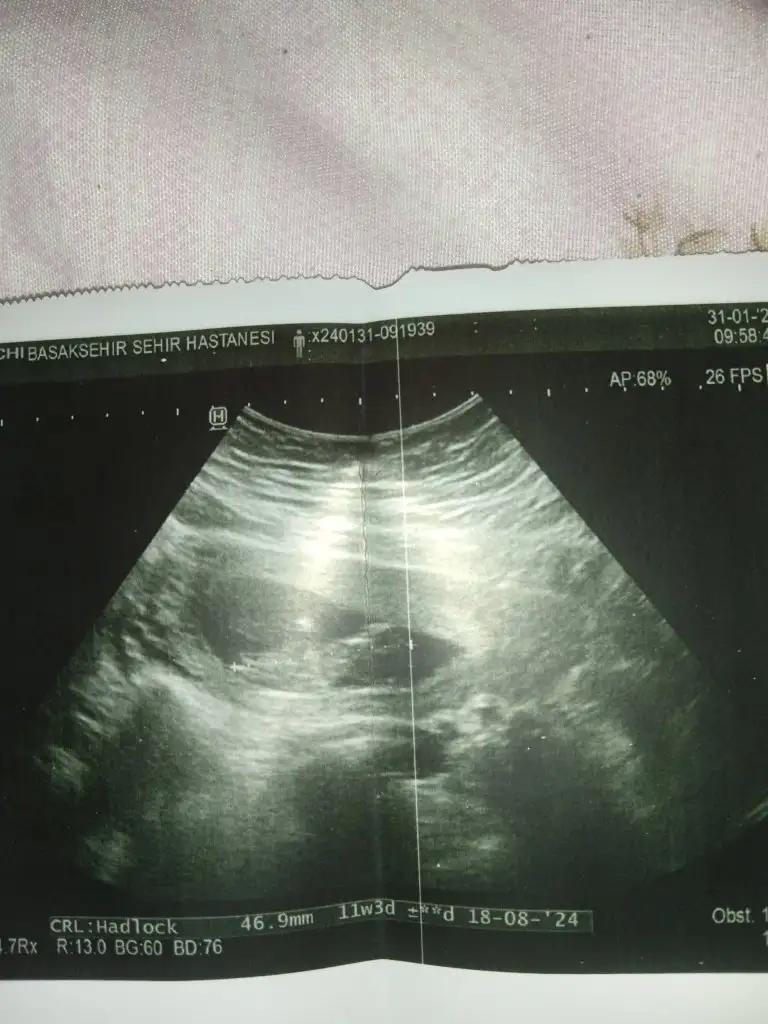

Canım bana da bakar mısın 11+1Kafası ne tsrafta anlasam söylerim de anlayamadım

Sizin bence erkek ama ben doktor değilim sadece kendi tecrübelerime dayanarak söylüyorum.Canım bana da bakar mısın 11+1